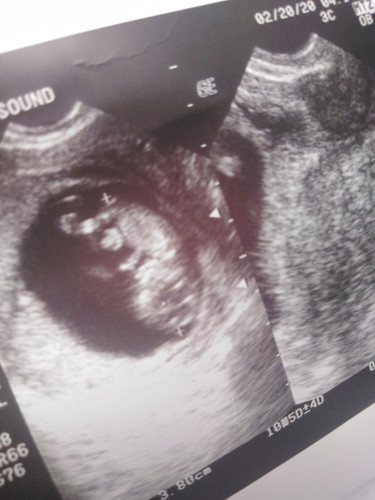

Retrochorionic Hemorrage

Good morning po mga momsh, 11 weeks pregnant me and 1st baby ko. Nagwoworry po kasi ako ng sobra. According to transvaginal ultrasound may bleeding po ako ng almost 11 cc na. Pero never naman po ako nagbleed talaga. May chance po ba mawala si baby? (??? wag naman po sana???) Naka bed rest and binigyan ako ni OB ng duphaston to intake 3x a day. Meron po ba kayo other suggestion in regards sa gantong case, na ano pa po dapat gawin ganun po? Thank you☺️